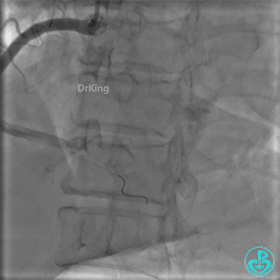

封堵后造影,PL分支远端血流中断。

心包内无明显积液。

术后超声未见心包积液。

1周后复查冠脉造影

PL主支通畅,远端一个小分支丢失,未见破口存在。